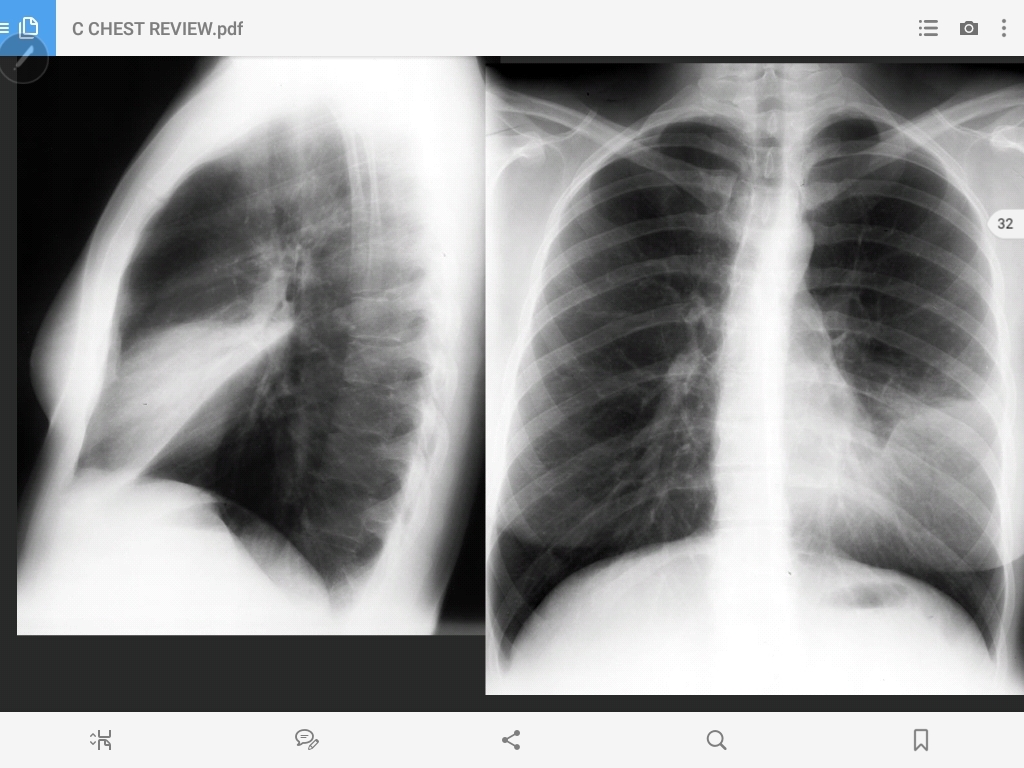

bullous emphysema

emphysema